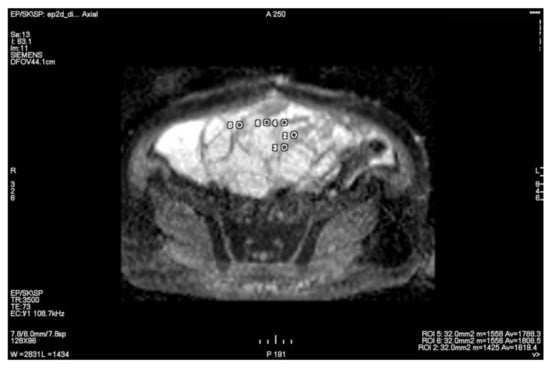

3.1. Primary Tumor DWI